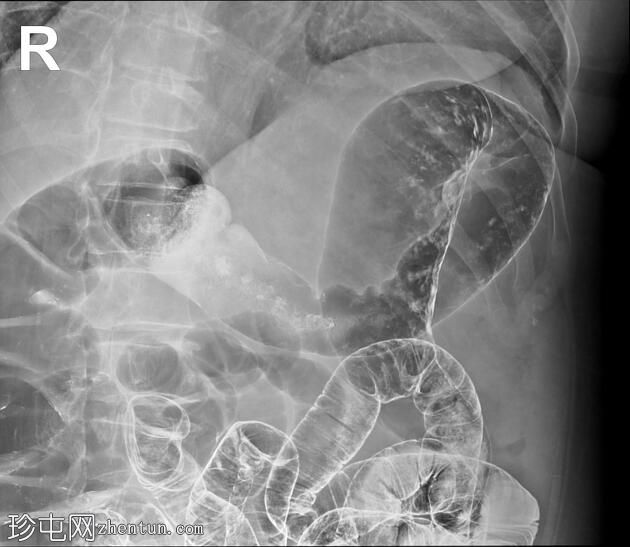

斜位

结肠异常表现包括结肠袋皱襞消失,使其外观模糊,呈铅管样改变。

其他异常表现包括降结肠和乙状结肠肠袢狭窄,以及横结肠和降结肠多处黏膜糜烂(双对比增强图像可见)。

未见肿块或瘘管形成。

升结肠外观正常,结肠袋皱襞完整。